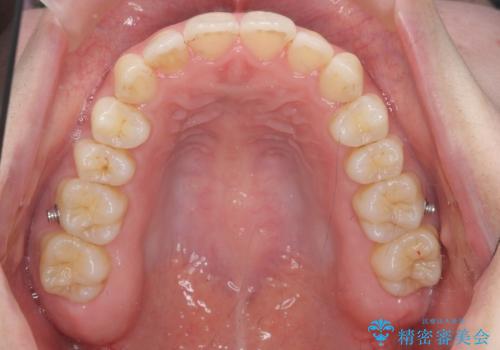

- インビザライン

今回は、下の歯を健康に支障が出ない範囲でわずかに削合し、並べるようにしました。(ディスキングといいます)

前歯のがたつきもしっかり治り、喜んでいただけました。

下の親知らずは虫歯になっていたため矯正前に抜歯しています。